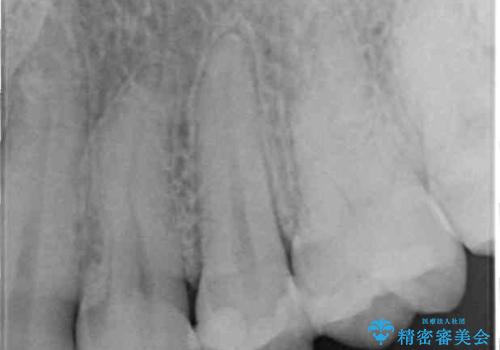

左上奥と右下奥に治療中の歯があり、虫歯を取っている途中で仮詰めの材料が充填されている状態でした。

仮詰め材を外すと虫歯が残っていたので、全てを取り除いた後に、ゴールドインレーの型どりを行いました。

当初はセラミックインレーによる修復治療を希望されいましたが、カウンセリングの結果、審美性よりも安定性を優先され、PGAインレー(ゴールドインレー・白金加金合金インレー)による治療を行うこととしました。